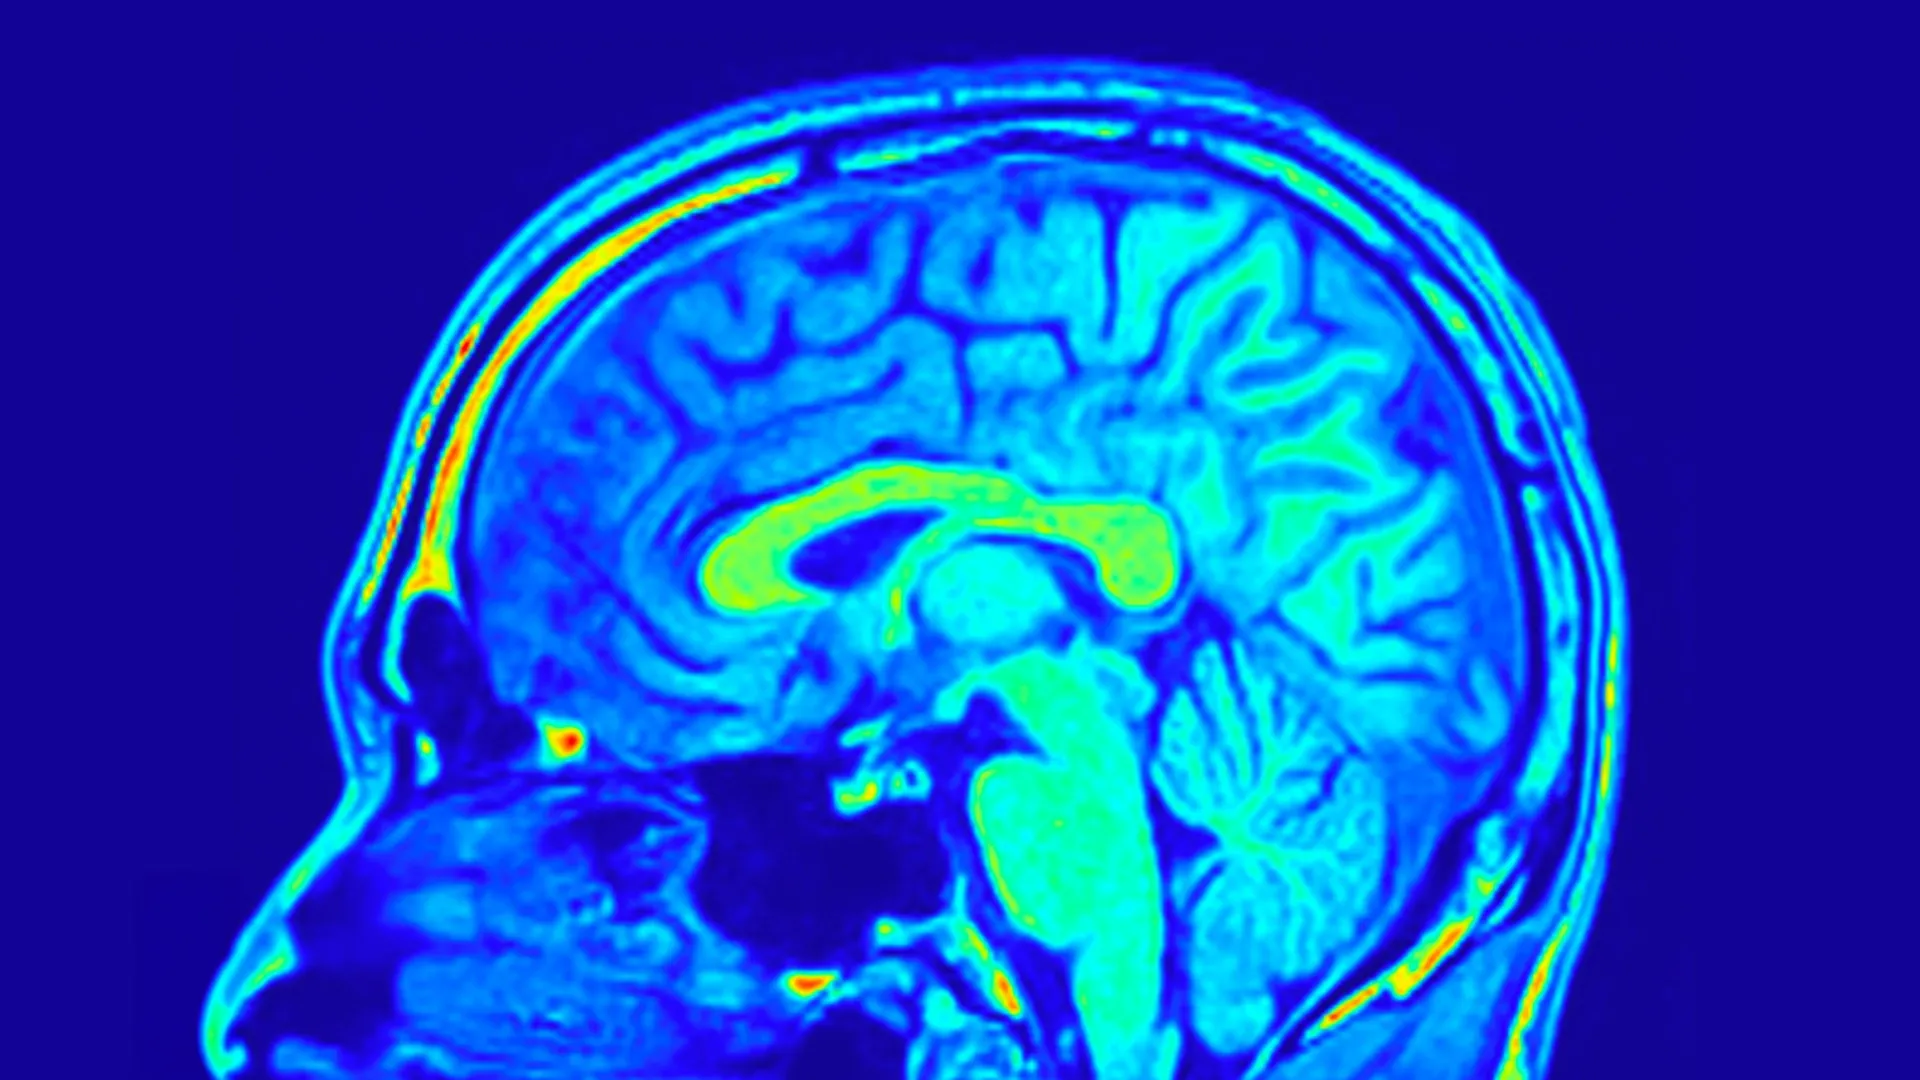

Para acompanhar os resultados, a equipe mediu a gravidade da depressão usando a Escala de Avaliação de Depressão de Hamilton (HAMD-24), um questionário clínico amplamente utilizado. Eles também coletaram amostras de sangue periférico e realizaram exames de ressonância magnética do cérebro para examinar mudanças na estrutura e na biologia do cérebro.

Os dados de imagens cerebrais revelam insights mais profundos. Os pesquisadores descobriram que redes específicas formadas por estruturas cerebrais previram mudanças nos escores de depressão em ambos os grupos de tratamento. Estas redes refletem a forma como as diferentes regiões do cérebro estão organizadas e conectadas.

Ainda mais surpreendente é que certos padrões cerebrais eram preditivos apenas para pacientes que tomavam pílulas Yueju. Esses padrões são baseados na profundidade do sulco e na espessura cortical, que descrevem o dobramento da superfície do cérebro e a espessura de suas camadas externas. Ambas as características estão relacionadas ao desenvolvimento e função do cérebro. Análises mais aprofundadas revelaram que a rede visual do cérebro desempenha um papel particularmente importante na previsão de melhorias nos sintomas depressivos e nos níveis de BDNF nos tratados com a pílula Yueju.

Em conjunto, as descobertas sugerem que os padrões de redes cerebrais identificados através de exames de ressonância magnética podem ajudar a prever como os pacientes com TDM responderão ao tratamento com a pílula Yueju. Esta abordagem vai além da tomada de decisão baseada em sintomas e aponta para um tratamento antidepressivo mais personalizado.